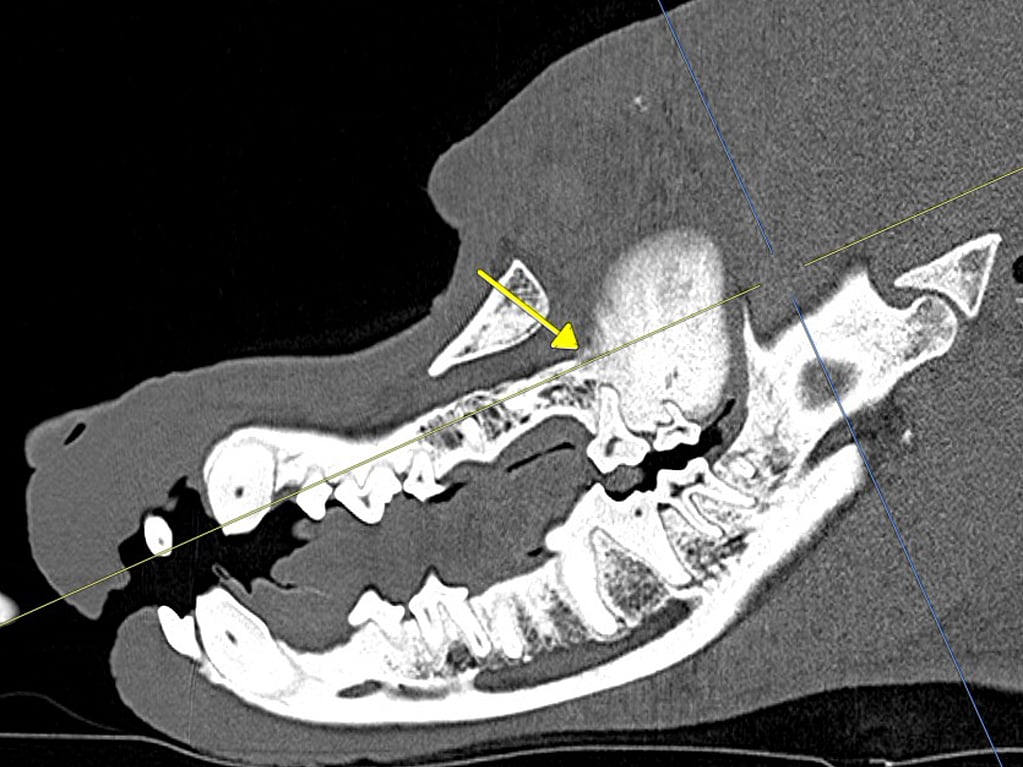

Er is voor een aanvullend onderzoek met behulp van een CT-scan gekozen om de precieze uitbreiding en structuur van de tumor te evalueren. Voorafgaande aan de chirurgie is het van belang om inzicht te krijgen hoe groot zo’n massa is, waar die precies groeit en welke anatomische structuren erbij betrokken zijn, Op die manier konden ons chirurgen samen met de radiologe een gedetailleerd behandelingsplan voor Yaro maken. De CT-scan van kop en thorax werd beoordeeld door dierenarts specialist Diagnostische Beeldvorming, Ilse Tiemessen. Er was een grote (ca. 4 cm in diameter), goedbegrensde massa met bot attenuiteit zichtbaar uitgaande van de linker caudale maxilla ter hoogte van de molaren. De massa breidde zich uit in het retrobulbaire gebied en in de recessus maxillaris. De mandibulaire en retropharyngeale lymfeknopen waren niet vergroot en in de thorax werden geen metastasen in de longen gezien.

Sagittale MPR van linker maxilla toont de grote en goed omschreven benige massa uitgaande van de linker caudale maxilla thv de molaren. Verder is zichtbaar dat de afwijkende botstructuren de alveolen van 208 en 209 omgeeft.